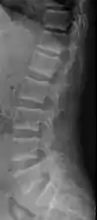

Renal osteodystrophy is usually diagnosed after treatment for end-stage kidney disease begins; however the CKD-MBD starts early in the course of CKD.[1][6] In advanced stages, blood tests will indicate decreased calcium and calcitriol (vitamin D) and increased phosphate, and parathyroid hormone levels. In earlier stages, serum calcium, phosphate levels are normal at the expense of high parathyroid hormone and fibroblast growth factor-23 levels. X-rays will also show bone features of renal osteodystrophy (subperiostic bone resorption, chondrocalcinosis at the knees and pubic symphysis, osteopenia and bone fractures) but may be difficult to differentiate from other conditions. Since the diagnosis of these bone abnormalities cannot be obtained correctly by current clinical, biochemical, and imaging methods (including measurement of bone-mineral density), bone biopsy has been, and still remains, the gold standard analysis for assessing the exact type of renal osteodystrophy.[6][16]